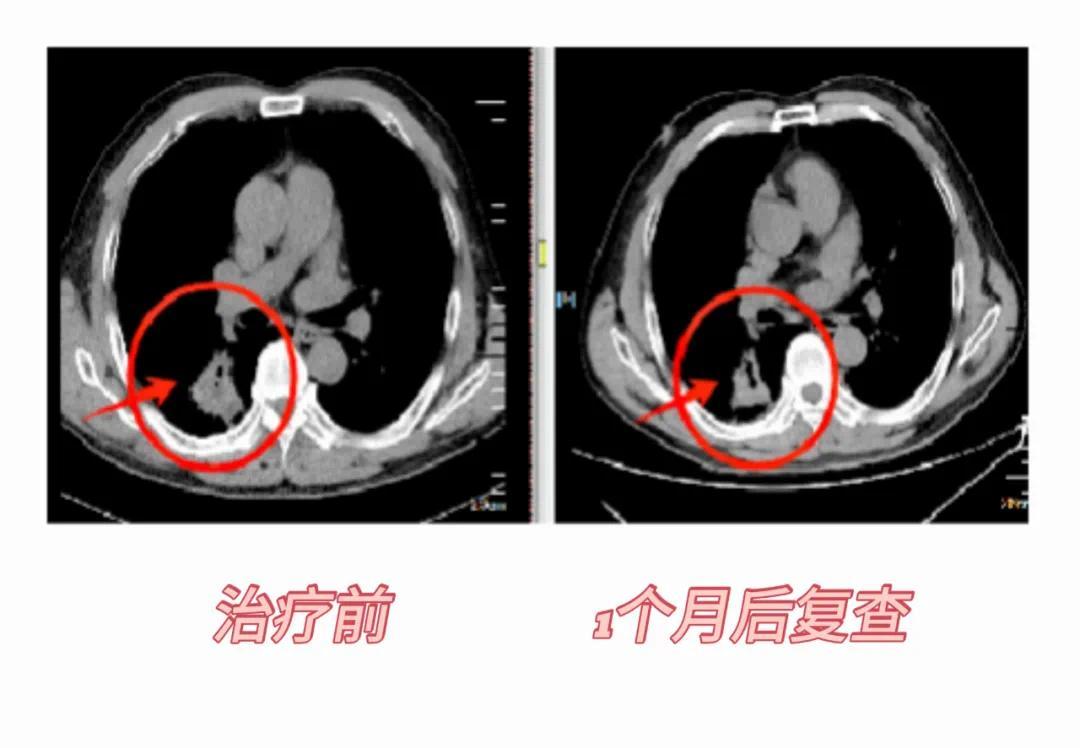

射波刀肺部病例:患者男性,58岁,胸部CT:右肺下叶背段见团块状高密度灶,边缘可见分叶及毛刺,大小约3.6*4.0cm;病理示:低分化腺恶性肿瘤。患者肺功能差不适合手术,选择射波刀治疗,1个月后复查病灶缩小,6个月后病灶进一步缩小,1年零3个月后病灶消失。